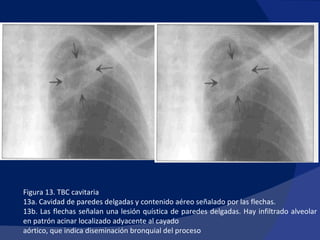

Las cavernas TBC corresponden a tuberculomas que se han comunicado con la vía aérea, desocupando en ella parcial o totalmente su contenido caseoso. Constituyen la característica probablemente más importante de la TBC Postprimaria, implica la salida del BK del entorno intracelular (en los macrófagos), diseminación endobronquial con compromiso de otras zonas del pulmón y abundante expectoración del bacilo

Figura 13. TBC cavitaria 13a. Cavidad de paredes delgadas y contenido aéreo señalado por las flechas. 13b. Las flechas señalan una lesión quística de paredes delgadas. Hay infiltrado alveolar en patrón acinar localizado adyacente al cayado aórtico, que indica diseminación bronquial del proceso